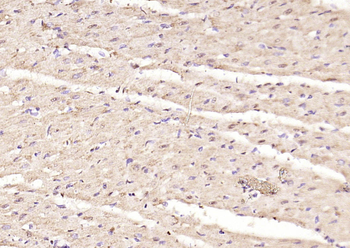

ICC, IF, IHC-Fr, IHC-P, WB

Mouse, Rat

Human, Mouse, Rat

Rabbit

Recombinant

Unconjugated

50 μl, 100 μlPhospho-Smad3 (Thr179) Rabbit Polyclonal Antibody [orb313112]